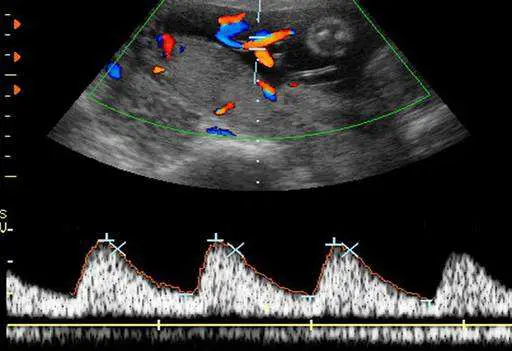

21 歲孕婦,G1P0 ,妊娠 38 週,接受杜卜勒超音波檢查,結果如圖所示,其檢查名稱為下列何者?

A臍動脈血流速度波形

B胎兒上行主動脈血流速度波形

C胎兒主動脈彎血流速度波形

D胎兒降主動脈血流速度波形

本題圖片為**彩色杜卜勒雙功超音波(color Doppler duplex ultrasound)**影像,包含上下兩個部分:

上半部分(B-mode + Color Doppler):

- 灰階超音波背景下可見扇形掃描影像(腹部超音波),胎兒組織結構可見

- 影像中可見彩色血流訊號(color flow signals):紅/橙色代表朝向探頭方向流動的血流,藍色代表遠離探頭方向流動的血流

- 彩色血流訊號集中於臍帶走行區域,可見多段血管截面的彩色標記,提示臍帶(umbilical cord)切面

- 取樣框(sample volume)設置於臍帶血管上以獲取頻譜

下半部分(Spectral Doppler waveform):

- 顯示頻譜杜卜勒波形(spectral Doppler waveform),呈現典型的搏動性動脈血流波形

- 波形特徵:

- 呈現規則的週期性**高